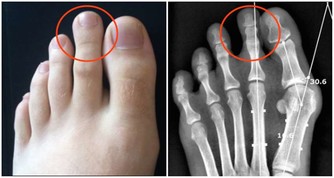

2.黑眼圈大而重

4.習慣性揉鼻子、揉眼睛、擠眉弄眼